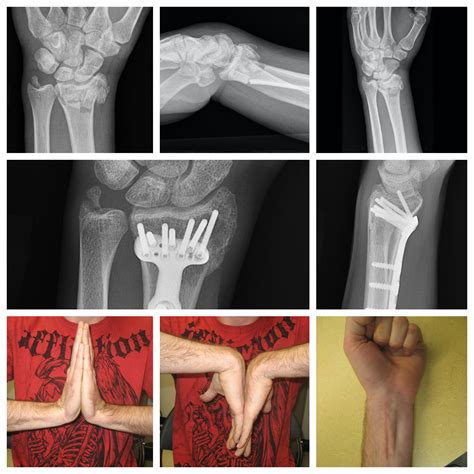

For more severe cases, surgical intervention—often called Open Reduction Internal Fixation (ORIF)—may be necessary. During this procedure, surgeons use metal pins, plates, or screws to hold the bone fragments together while they mend. This is typically required if the fracture is intra-articular (extending into the wrist joint) or if the bone is shattered into multiple pieces.

Recovery from a fracture broken wrist is a marathon, not a sprint. Once the bone has knitted back together—usually confirmed by follow-up X-rays—the focus shifts to restoring function. Long periods of immobilization in a cast lead to muscle atrophy and joint stiffness. Physical therapy is vital during the post-cast phase. Your therapist will guide you through exercises to:

Most patients start to see significant improvements within three to six months, though some minor aches and stiffness during cold weather may persist for a year or longer. Consistency with your home exercise program is the single most important factor in determining your long-term outcome. Neglecting therapy can result in a permanent loss of motion, which impacts daily tasks like typing, lifting, or gripping objects.